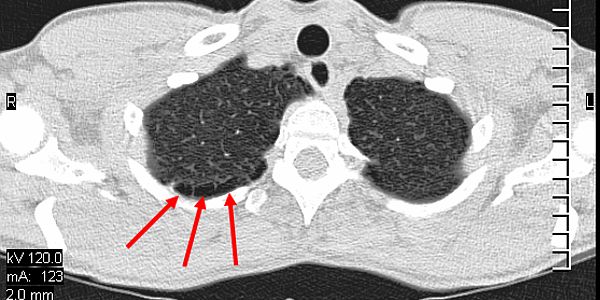

Immer gut Luft

Für uns Taucher ist die Lunge natürlich mit das wichtigste Organ. Daher sollte mit der ersten Tauchtauglichkeit die Lunge eines Tauchers eingehend überprüft werden. ... weiterlesen

Pulmonales Barotrauma

Das Hyperbare Medical Center in Sharm el Sheikh hat über die Jahre Hunderte von Tauchunfällen behandelt; ein Pulmonales Barotrauma ... weiterlesen

Tauchen mit Atemwegserkrankungen

In diesem Artikel werden die wichtigsten Fakten zur Tauchtauglichkeit sowie deren Einschränkungen bei entsprechenden Krankheitsphasen chronischer Lungenerkrankungen aufgezählt. ... weiterlesen